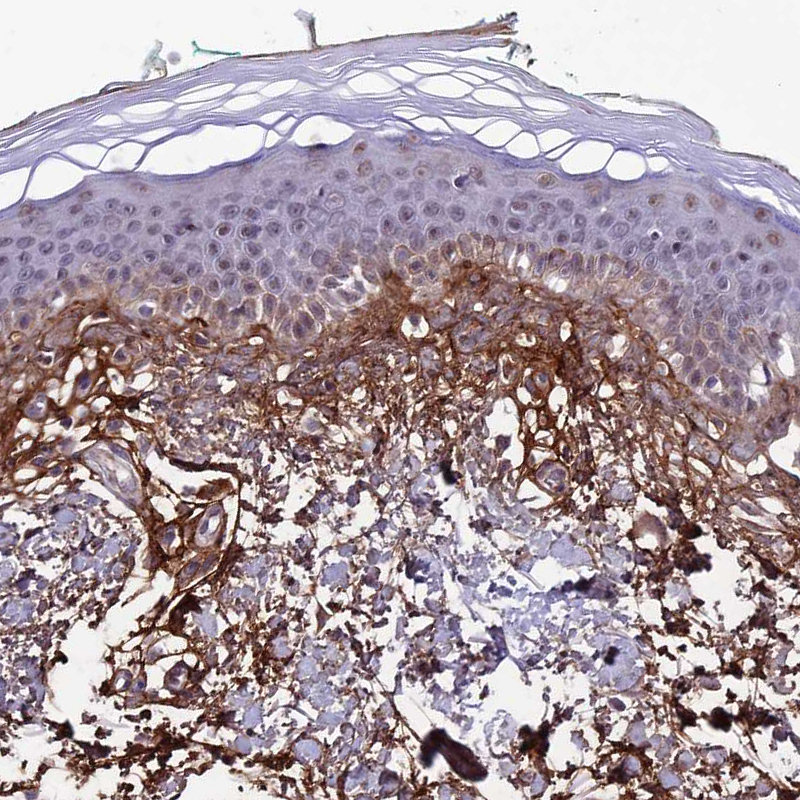

Immunohistochemical staining of human lung shows moderate to strong membranous positivity in pneumocytes.